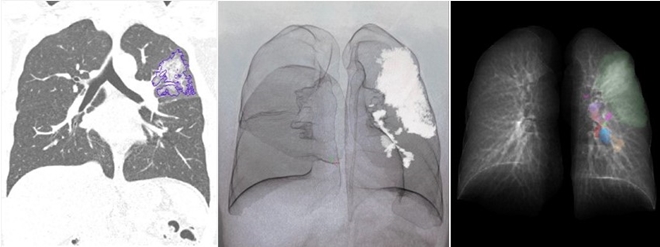

▲MEDIP PRO를 통해 자동 분석된 코로나 분석 이미지

메디컬아이피는 지난 3월 31일 'Radiology : Cardiothoracic imaging'에 게재된 논문 'Extension of Coronavirus Disease 2019 (COVID-19) on Chest CT and Implications for Chest Radiograph Interpretation'에 참여해, 핵심 기술이 집약된 소프트웨어 ‘MEDIP PRO(이하 메딥프로)’를 통해 코로나19 환자의 흉부 CT로 폐렴의 중증도를 분석하고 정량화할 수 있음을 입증했다.

MEDIP COVID19는 환자의 익명화된 CT 의료영상을 분석해 1분 내로 코로나19 폐렴을 자동으로 탐지, 분할, 정량화할 수 있는 소프트웨어로 코로나19 공동연구에 활용된 MEDIP PRO의 기술력에 기반해 개발됐다.